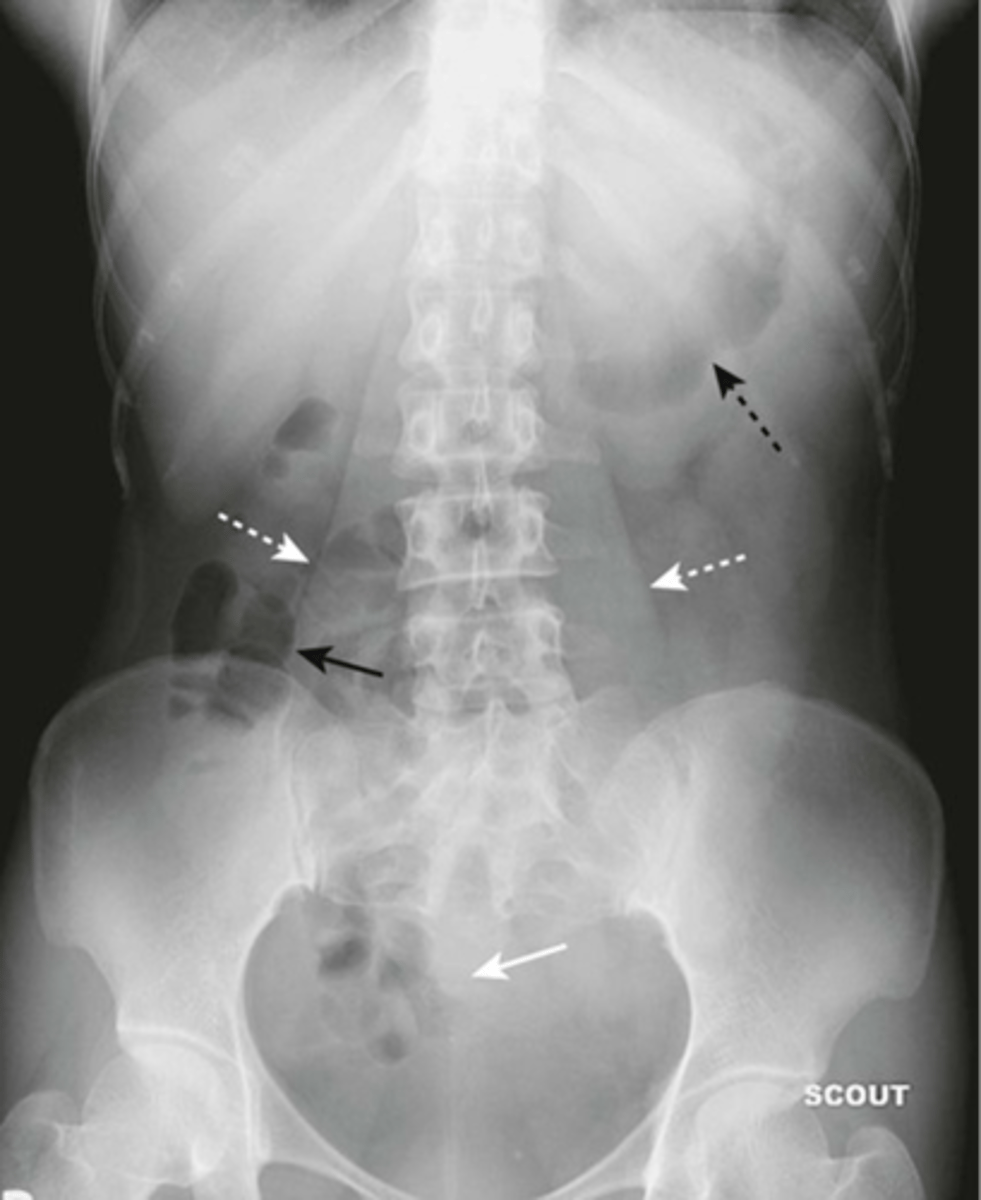

Normal bowel gas pattern

Normal supine AXR